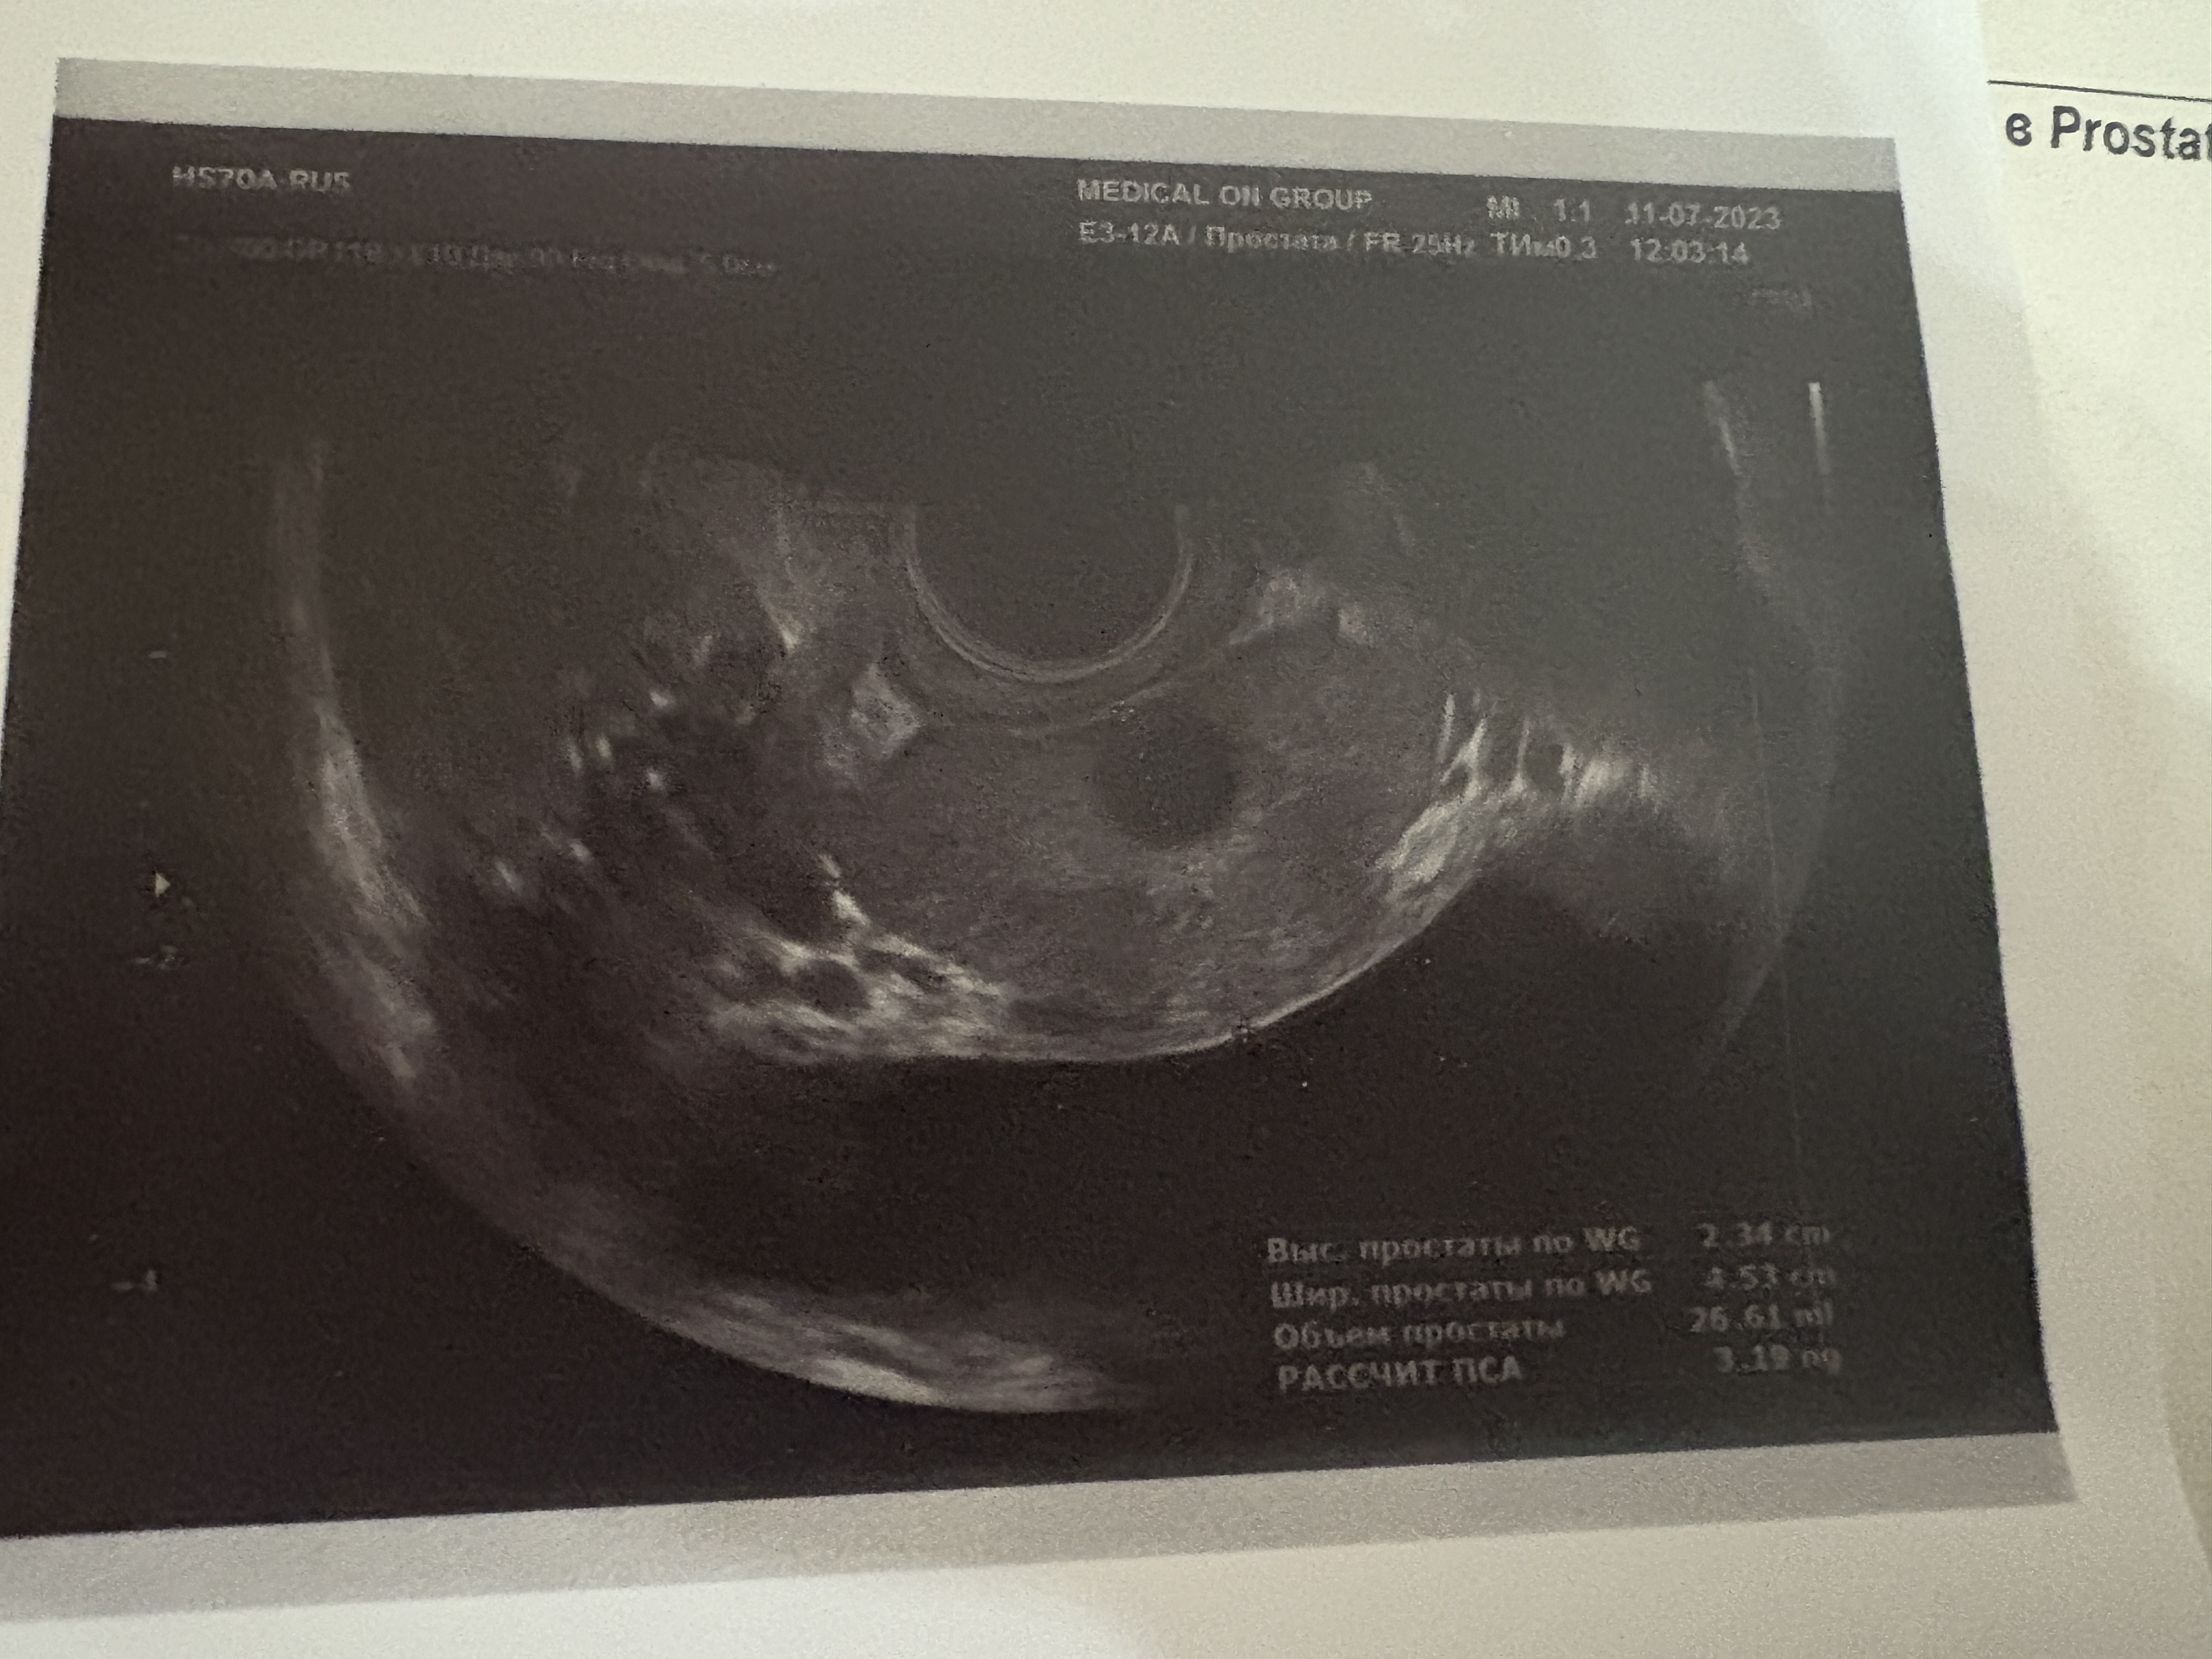

уролог направил сдать анализы и сделать допплерографию. По анализам все в порядке, кроме пролактина: он был в районе 700. На УЗИ-допплера показало, что у меня артериогенная ЭД с вторичной венозной утечкой (как объяснил узист, т.к. нету нормального притока к члену, все утекает, и поэтому член выглядит толще и меньше; фиброза, кстати, нет). В декабре 24-го назначили курс УВТ, и лечиться тадалом 5мг каждый день.